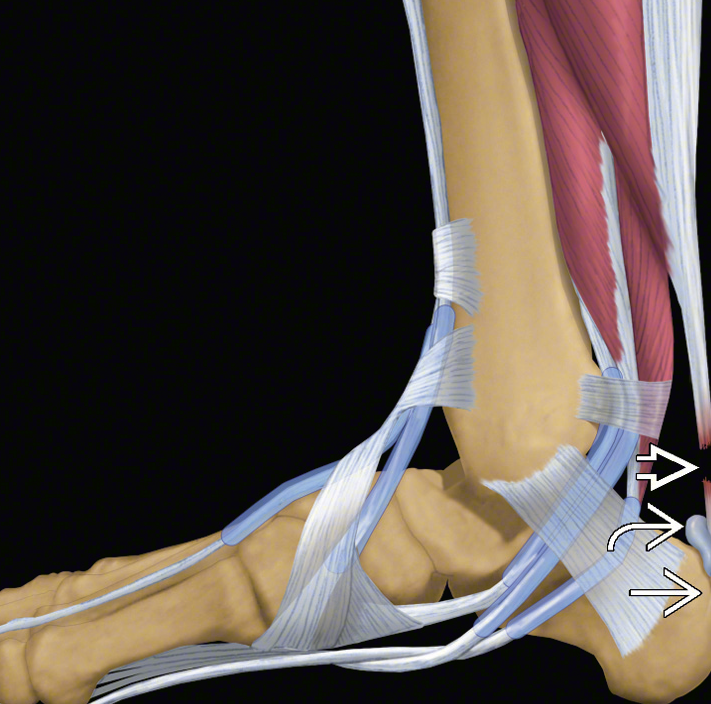

Aşil kopmasının A. Şematik görünümü, B. MR görüntüsü